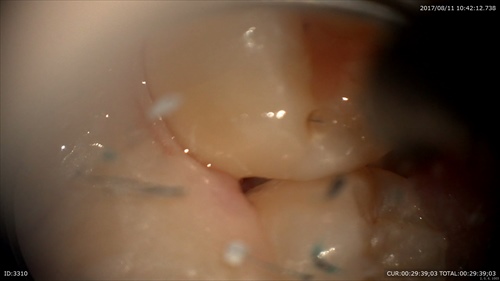

歯石発見!!

丁寧にデブライドメント